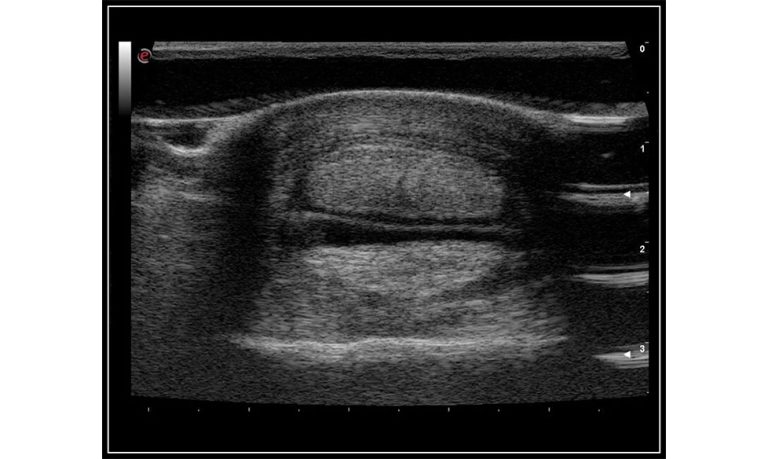

Ultrasound

Wide range of Ultrasound machines that suites a variety of applications from abdominal to rectal scans, we take in consideration how the world is moving towards mobility and mobile applications.

SonoScape Pro Pet E11

Smart Imaging

Introducing the first portable ultrasound with the C-Field+TM platform, redefining diagnostic imaging. Designed for veterinarians, it delivers unmatched clarity, ultra-fast processing, and seamless adaptability for all species. Experience Smart Imaging, Heartfelt Care—anywhere.

Equipped with cutting-edge veterinary software and optimized workflows, it embodies our commitment to Smart Imaging, Heartfelt Care – Wherever Their Journey Leads, with unparalleled performance and adaptability, this innovative system empowers veterinarians to provide exceptional care across all diagnostic applications,